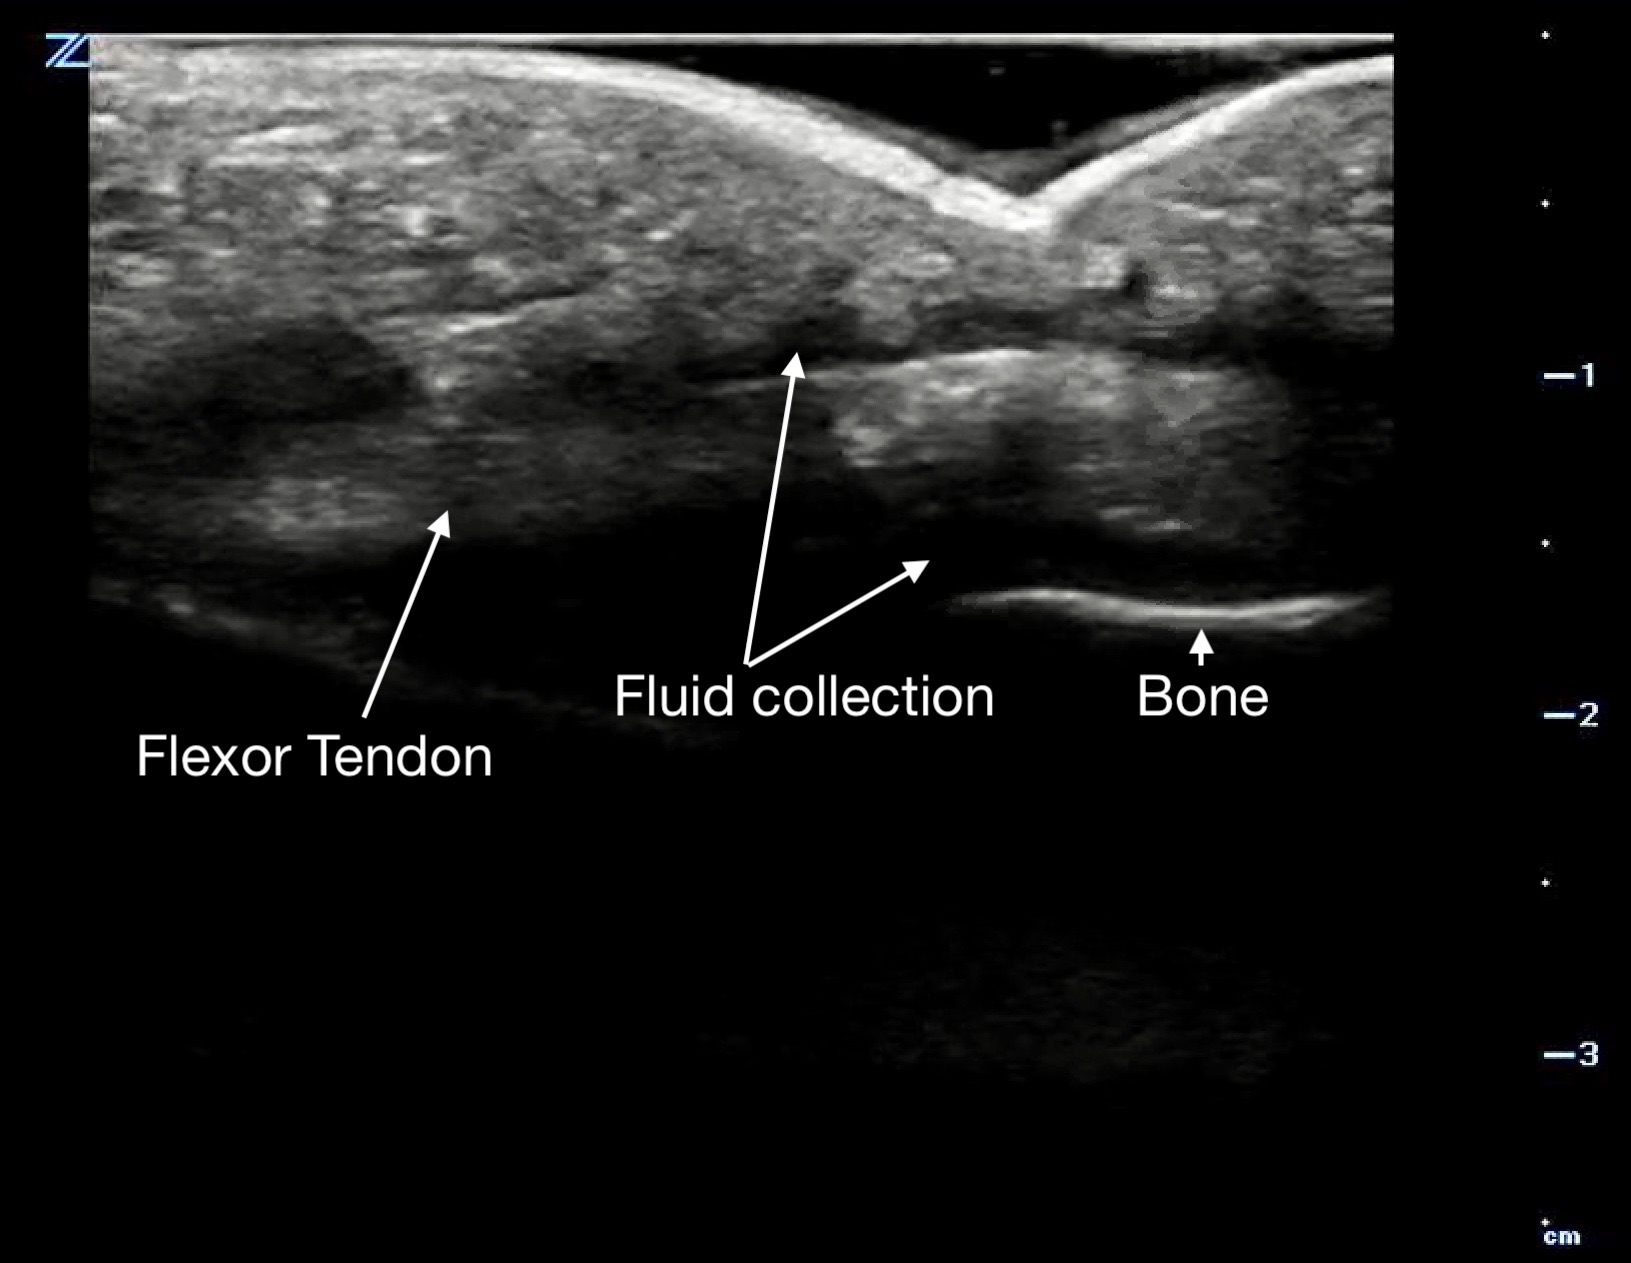

Tenosynovitis will appear as a thickened tendon and on short axis will have a halo of anechoic fluid surrounding it in the tendon sheath.

Figure 14a.

Flexor tenosynovitis demonstrated by the halo of fluid in the sheath surrounding the tendon

Figure 14b.

a long axis view with fluid above and below the flexor tendon.